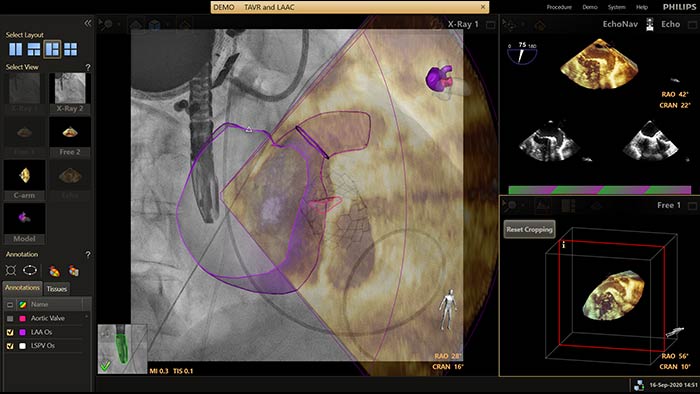

EchoNavigator heroriënteert en combineert echografie- en röntgeninformatie in één verbeterde visualisatie voor geleiding en beoordeling van de relatie tussen instrument en weefsel. Bij linkerhartoorsluiting (LAAO) maakt EchoNavigator het volgende mogelijk om het vertrouwen te vergroten en de efficiëntie te verbeteren: